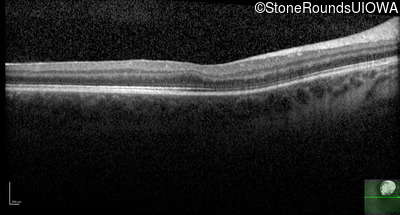

Age at visit: 5 weeks (Visit 2)